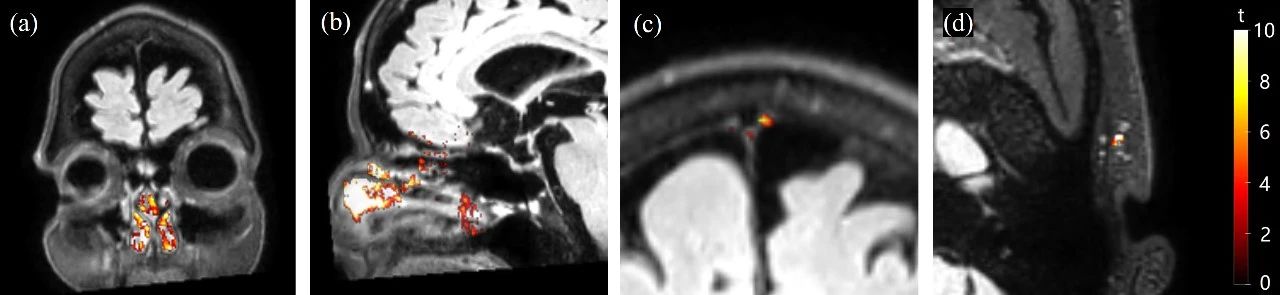

85bfdbcf9624562a69b5e07797db86d1.jpg

代表性的体素图显示了一名受试者在cDSC MRI中由GBCA诱导的显著信号变化。

显著体素的t分数被叠加在GBCA后FLAIR图像的嗅觉区域(a,b)、副矢状硬脑膜(c)和淋巴结(d)上。